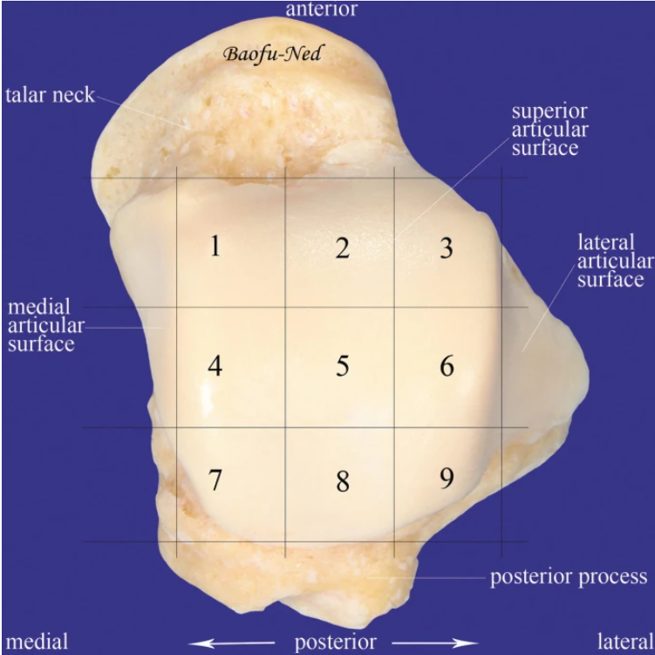

Рис. 1. Таранная кость (вид сверху). Обширная хрящевая поверхность покрывает около 60% кости

Медиальный купол таранной кости поражается в 56-67% случаев, латеральный — в 26-36%, центральный — менее чем в 10%. Билатеральные повреждения встречаются в 10% случаев.

Характер повреждения зависит от локализации:

- Медиальные ОХП — чаще глубокие, чашеобразные (cup-shaped), более крупные, расположены в задней трети купола. В 30-38% случаев травма в анамнезе отсутствует.

- Латеральные ОХП — чаще поверхностные, пластинчатые (wafer-shaped), более мелкие, расположены в передне-средней трети купола. 93-98% имеют чёткую связь с травмой.

Эти морфологические различия имеют принципиальное значение как для понимания патогенеза, так и для выбора хирургического доступа.